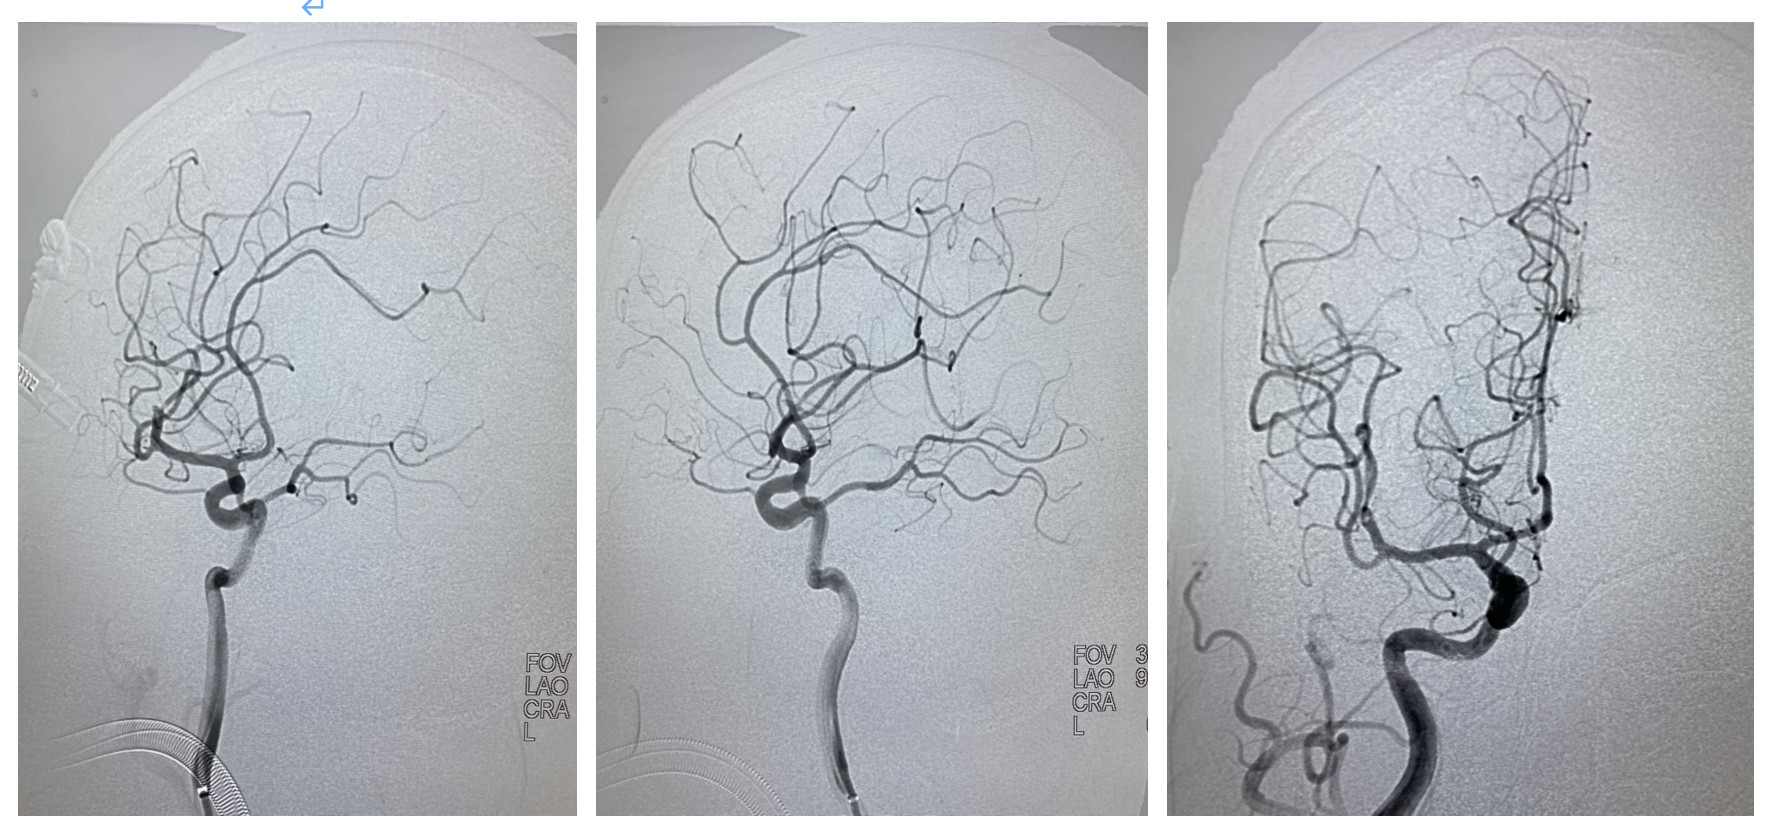

1、术中造影可见右侧大脑中动脉M2段上干闭塞,同侧大脑前无明显代偿,故不考虑狭窄,判断为血栓形成,尝试抽拉结合开通血管。

2、心玮吞川抽吸导管到达海绵窦段,微导管在微导丝的引导下无阻力进入较为平滑的M2远端,冒烟证实在血管真腔。

3、心玮4-20取栓支架到位释放,等待5分钟,在支架铆钉及微导管的支撑下,逐步跟进抽吸导管至M2闭塞处,撤出微导管,关闭滴注,利用SWIM技术,整体将取栓系统撤出体外,复查造影血流2b级,正位看局部似乎还有血栓,侧位及斜位看,似乎还有1支未通,给予动脉内替罗非班10ml/10分钟。

4、给予替罗非班后为进一步了解病变,行3D造影,最终证实M2分叉部一共有4支,开通3支,还有1支闭塞,指向额叶供血。